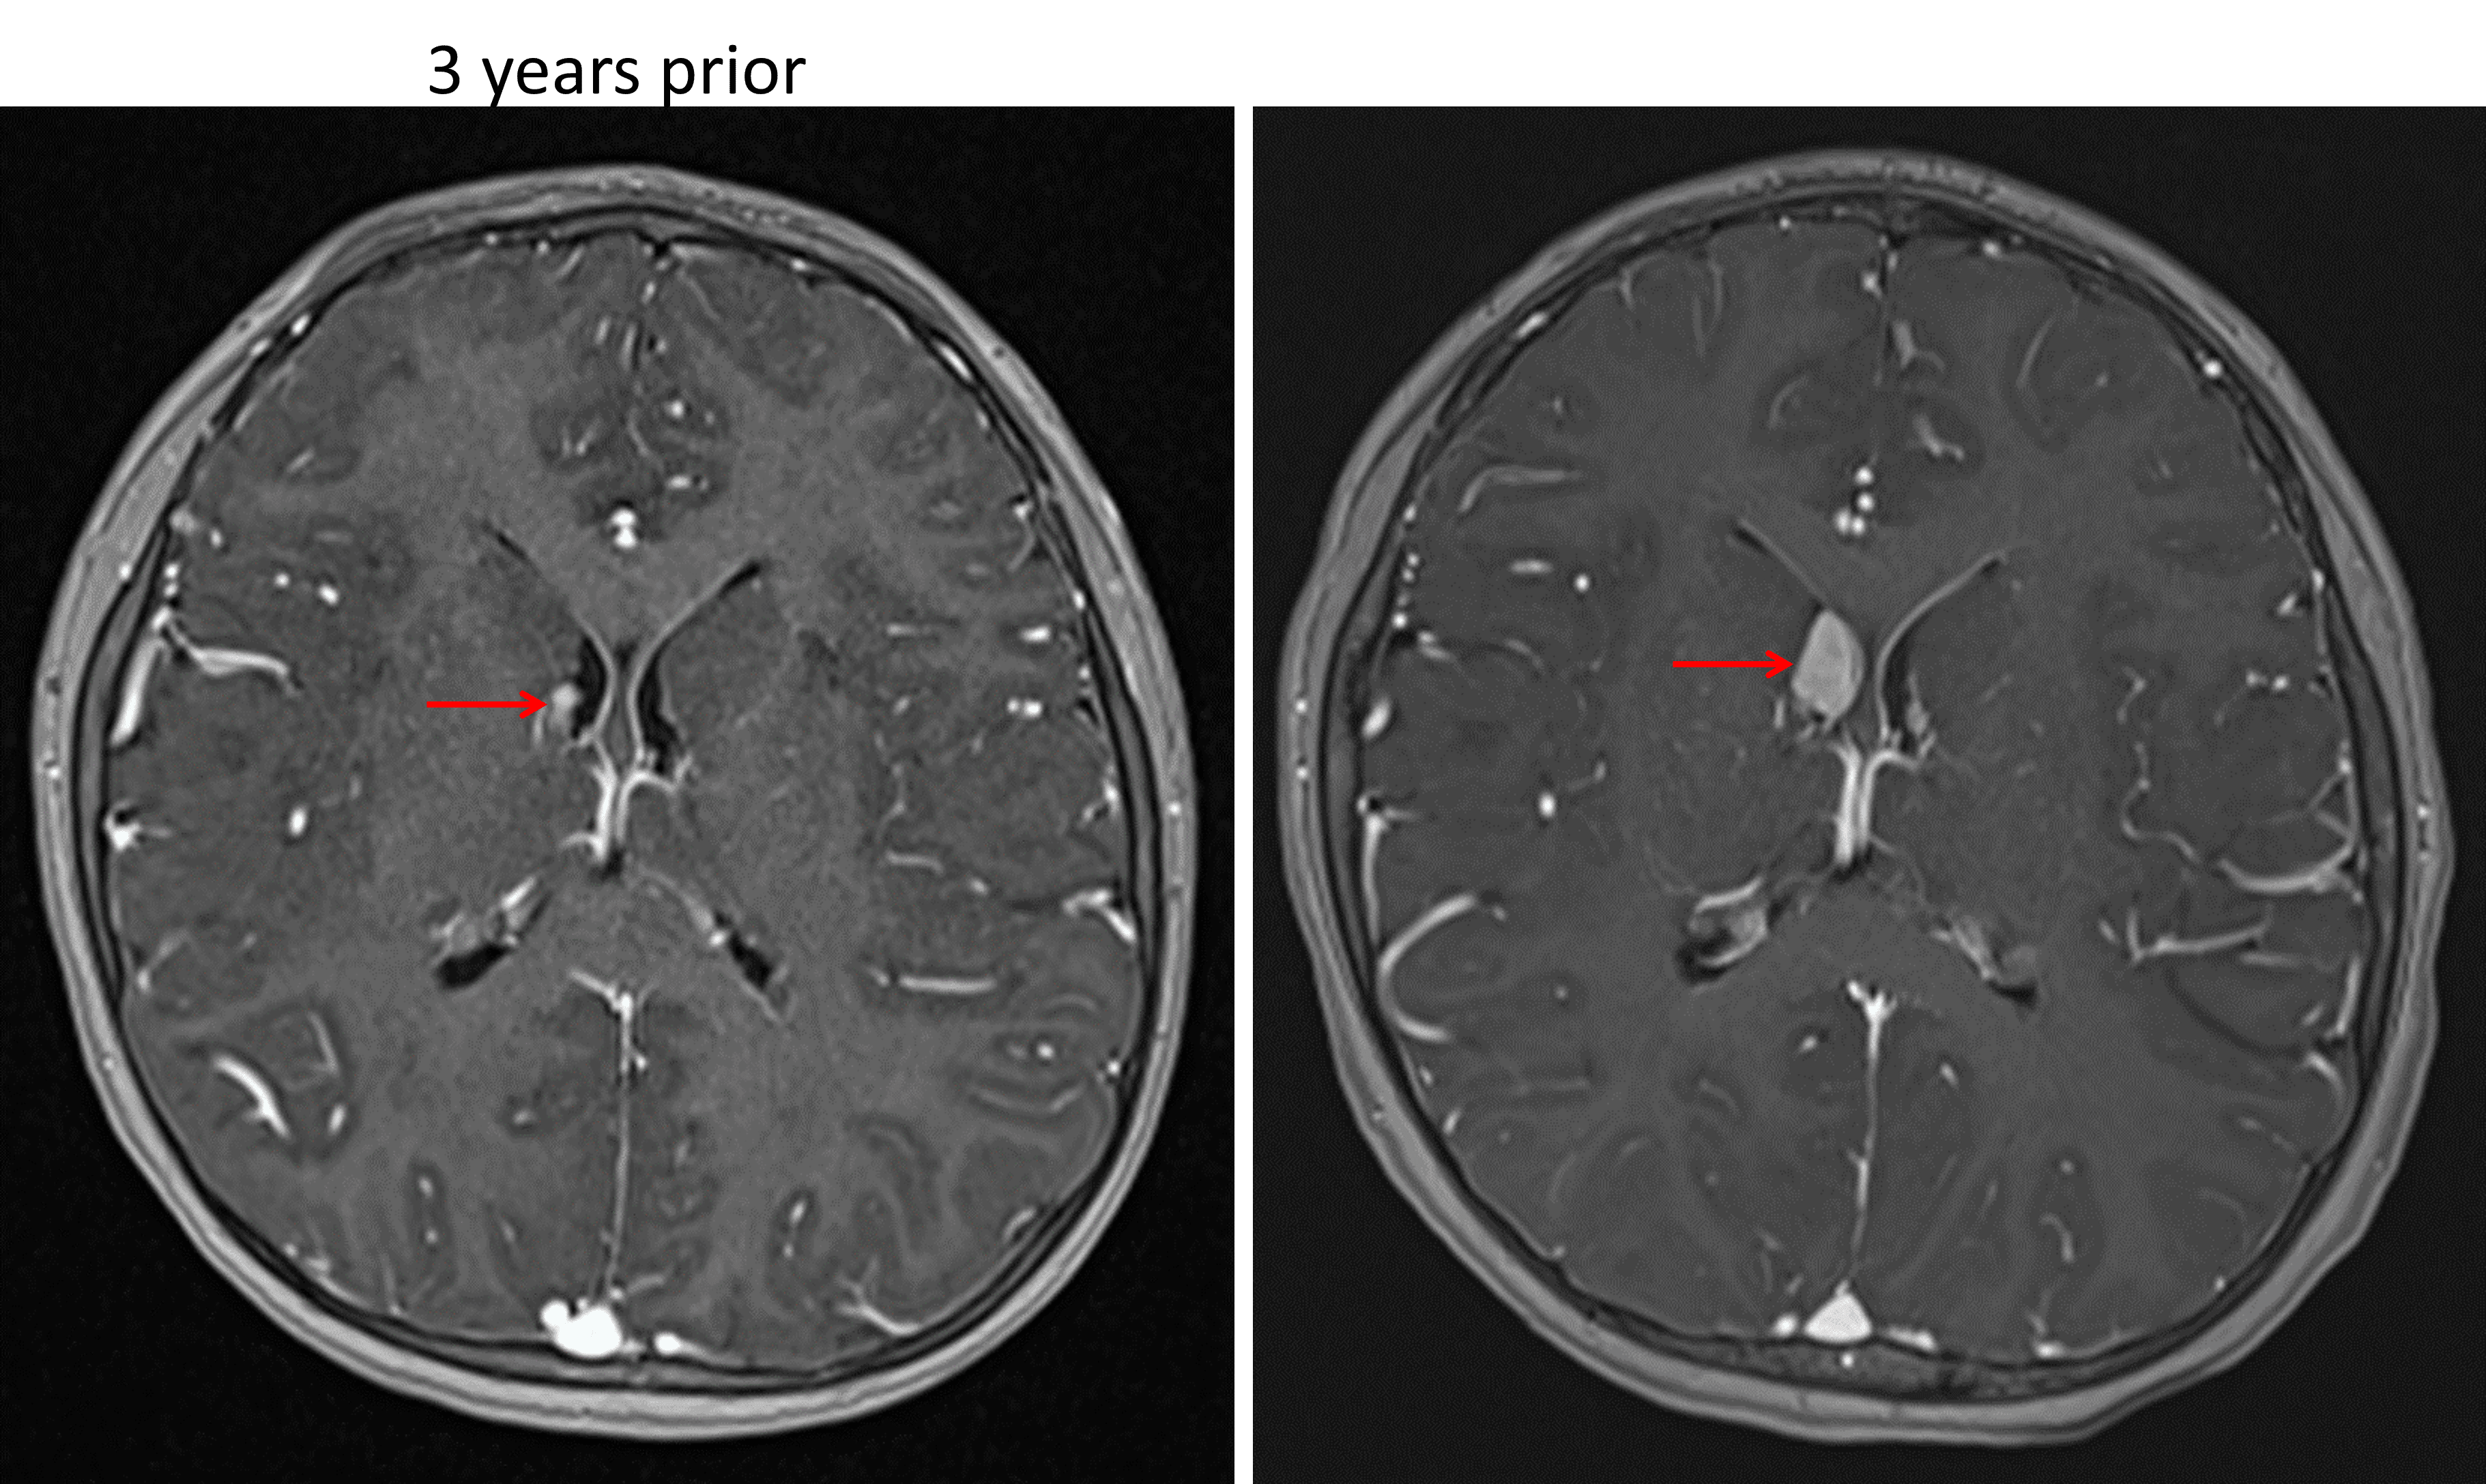

Indication: Screening MRI in patient with tuberous sclerosis

• Interval enlargement of an enhancing subependymal nodule near the right foramen of Monro measuring 1.5 x 1 cm

Enhancing subependymal nodule near the right foramen of Monro (red arrows) which demonstrates growth over a 3-year period, concerning for a subependymal giant cell astrocytoma in this patient with tuberous sclerosis.

Subependymal giant cell astrocytoma (SEGA)